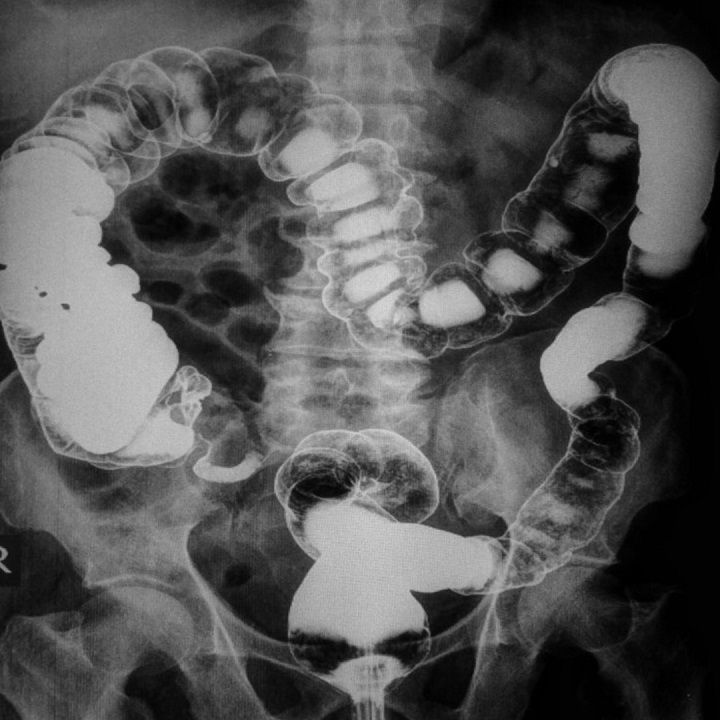

10.000 ember – ennyivel növekszik évente azok száma, akiknél vastagbélrákot diagnosztizálnak.

70% - a diagnosztizáltak kb. 70%-a 5 éven belül bele is hal a kórba, holott időben felfedezve...

5000 ember – élete lenne megmenthető évente a jó prevencióval, a rendszeres szűrővizsgálatokkal.

50 év felettiek - minden Nő, és Férfi egyaránt a veszélyeztetettek csoportjába tartozik.